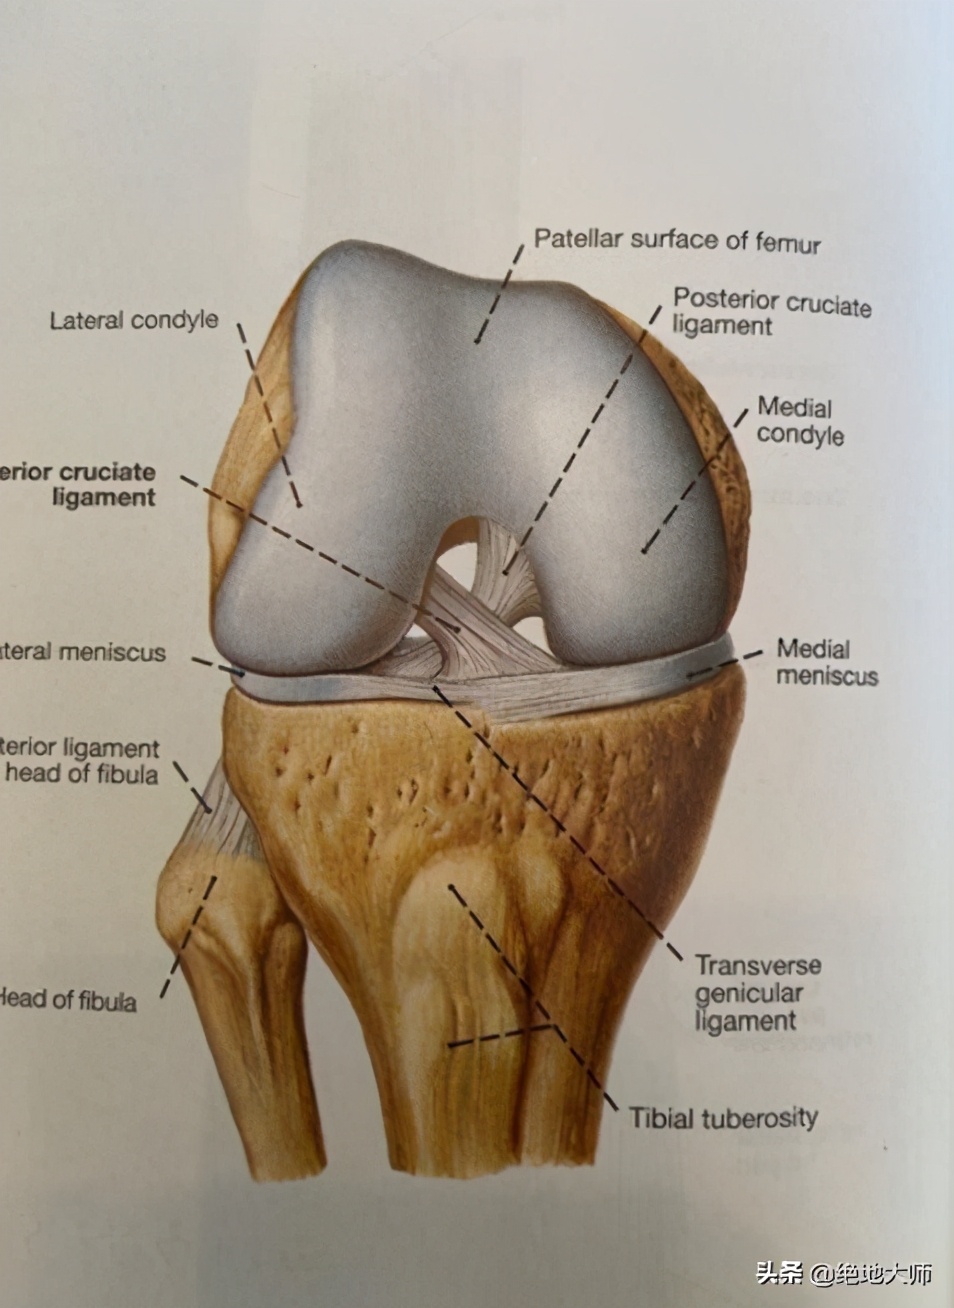

CLASSIFICATION: TRAUMATIC & NON-TRAUMATIC 分类:创伤性和非创伤性

ANATOMY 解剖

4. ANATOMY: TIBIOFEMORAL JOINT 解剖:胫股关节

HOUSES MEDIAL & LATERAL MENISCUS 包容内外侧半月板

CONNECTS LIGAMENTS 连接韧带

ACL, PCL, LCL, MCL

6. LIGAMENTS 韧带: ACL/PCL

ACL – ANTERIOR CRUCIATE LIGAMENT 前交叉韧带

PREVENTS ANTERIOR TRANSLATION OF THE TIBIA RELATIVE TO THE FEMURE

预防胫骨相对于股骨向前移位

PCL – POSTERIAL CRUCIATE LIGAMENT 后交叉韧带

PREVENTS POSTERIOR TRANSLATION OF THE TIBIA 预防胫骨向后移位

LCL – LATERAL COLLATERAL LIGAMENT 外侧副韧带

MEDIATES LATERAL TRANSLATION OF THE TIBIA RELATIVE TO THE FEMUR

介导胫骨相对于股骨向外侧移位

MCL – MEDIAL COLLATERAL LIGAMENT 内侧副韧带

MEDIATES MEDIAL TRANSLATION OF THE TIBIA RELATIVE TO THE FEMUR

介导胫骨相对于股骨向内侧移位

7. LIGAMENTS 韧带 LCL/MCL